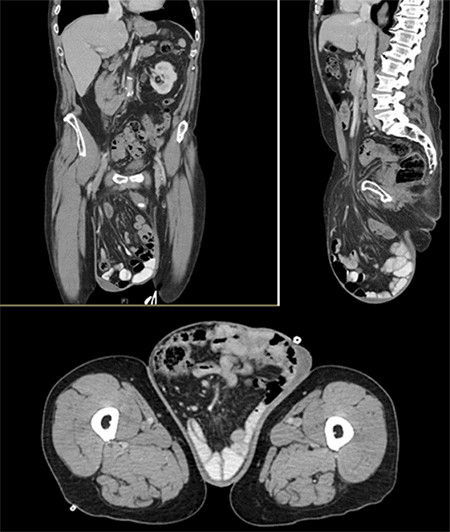

A 71-year-old Caucasian male presented with a giant inguinoscrotal hernia (Figure 1). Contrast enhanced CT imaging revealed an inguinoscrotal hernia with contents of large and small bowel, including the ileocecal valve (Figure 2).

Figure 2. Contrast enhanced CT of the abdomen and pelvis in coronal, sagittal, and axial views